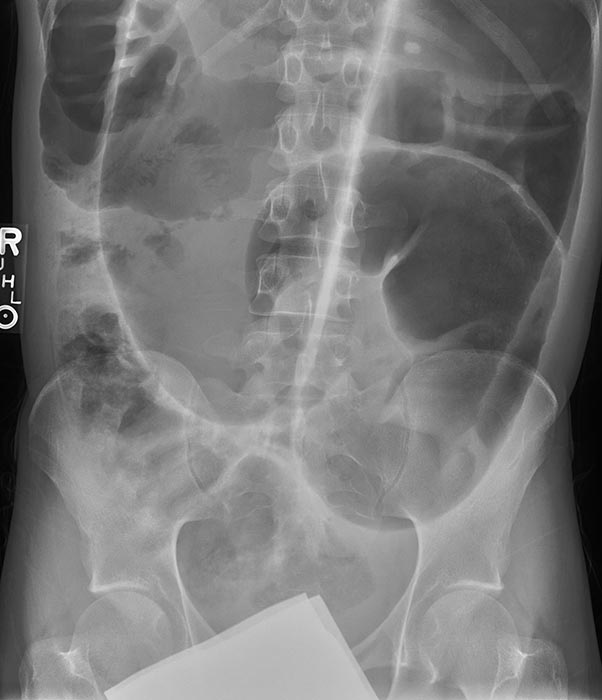

What is volvulus? (twist)

A twisting of a portion of the bowel that may cause obstruction and compromise blood supply.

What are the two major dangers of volvulus?

Bowel obstruction and compromised blood supply.

What can compromised blood supply lead to in volvulus?

Necrosis and gangrene.

Obstruction can cause severe distension leading to bowel perforation.

What are common symptoms of volvulus?

Severe abdominal pain, vomiting, and abdominal distension.